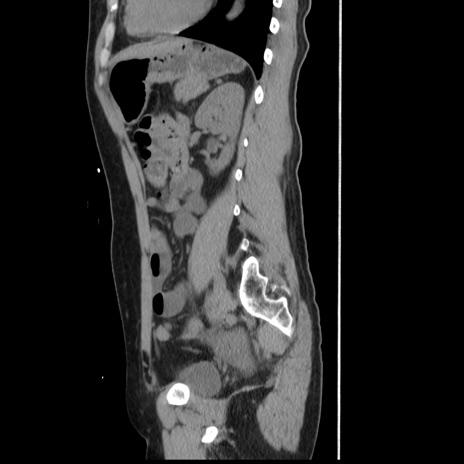

横断像

冠状断像